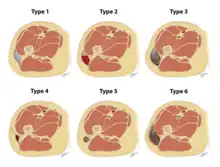

Drawings depicting the types of Morel-Lavallee lesions from the Mellando-Bencardino classification.

The Mellado-Bencardino classification can be used to describe a Morel-Lavallée lesion based on its MRI.[5] The classification categorizes the lesions into types.[8] The classification has six stages listed as Type I to Type VI.[5] The types do not align with specific treatments or outcomes.[4][8] The stages are based on multiple factors that can be observed on the lesion's MRI.[5] These factors include the following: the shape of the lesion, specific MRI features, and whether a capsule is present.[5][8]